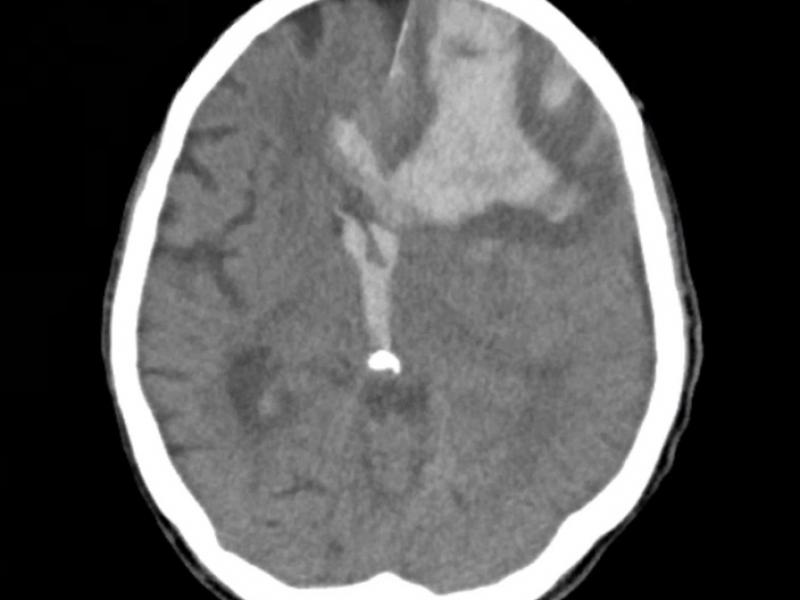

A 93 yo female with a history of afib and rivaroxaban